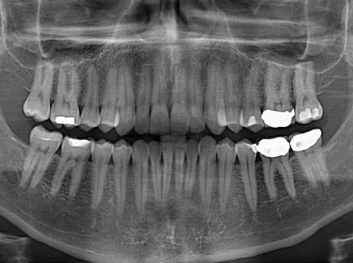

損壞的牙齒如何自我修復(fù)?近日,來自哈佛大學和諾丁漢大學的研究人員研發(fā)了能夠刺激牙齒干細胞再生的新型生物材料,而這種新材料研發(fā)成功的背后,正源于他們對牙齒如何實現(xiàn)自我修復(fù)這個課題的不斷探索。

據(jù)美國期刊《大眾科學(Popular Science)》報道,此種新型生物材料,不僅可以有效地取代傳統(tǒng)補牙填充物,刺激牙齒干細胞再生,患者也有望無需再接受根管治療,使蛀牙患者免除牙根感染或牙髓壞死的苦惱,一個全新的牙齒治療時代即將來臨。

Adam Celiz,是來自諾丁漢大學的研究人員,他和同事開發(fā)的這種新型合成生物材料,能刺激干細胞在牙髓部的生長。與普通材料一樣,這種合成材料被填充到牙齒并用UV光硬化。

在體外測試中,材料刺激干細胞進入牙本質(zhì)的增殖和分化速度,促進形成牙齒骨組織。研究人員認為,一旦材料在受損牙齒中應(yīng)用,這些干細胞可以自動修復(fù)來自填充物上的損壞。在本質(zhì)上,該生物材料將使牙齒自愈。

在未來,Adam Celiz說,可再生材料能制成各種填充物以便受損牙齒的自身治愈,降低補牙失敗率,甚至會消除大部分人對根管治療的需要。